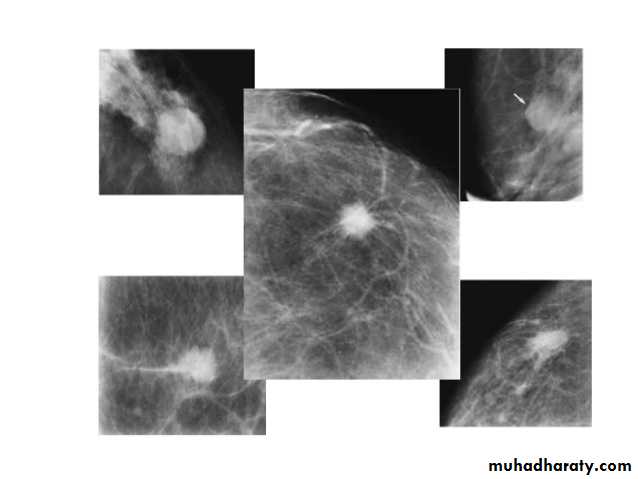

Radiographic features

Mammogram

spiculated hyperdense lesion

oval/lobulated lesion

microcalicifications

ILC is more often multicentric and bilateral (10-15%). Therefore imaging evaluation of the contralateral breast is crucial. There can be very subtle changes such as progressive shrinkage or enlargement or reduced compressibility of the involved breast. Imaging often underestimates the disease.

Mammography

The sensitivity of mammography for the detection of ILC reportedly ranges between 55-80% 8. Because of the limitations of mammography in detecting ILC, other modalities, such as sonography and MR imaging, are being used in evaluating clinically suspicious findings and known cancers to assess the extent of disease. ILC are more commonly seen on the craniocaudal (CC), compared to the mediolateral oblique (MLO).

Invasive ductal Ca invasive lobular CA